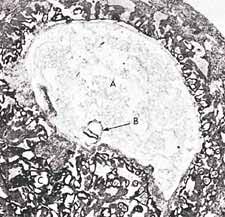

A Korán Allah szava, amelyet Mohammed Prófétának (Allah áldása és békéje Reá) küldött le a Földre Gábriel angyal segítségével. Mohammed Próféta (Allah áldása és békéje Reá) feladata volt, hogy átadja az Iszlám üzenetét az emberiségnek. A Korán így Allah egyik csodája, olvasása közelebb viszi a hívőket Urukhoz, s közbenjáró is lesz a hívőkért az Ítélet napján. A Korán csodás a történetei terén, minden korábbi írásnál sokkal teljesebb, pontosabb leírást ad a Paradicsomról és a Pokolról is, az egész Túlvilágról, a Feltámadás Napjáról, arról, hogy mi történik a halál után. Csodás a törvénykezés terén, az élet valamennyi területére nézve gyakorlati útmutatót is tartalmaz. Egyedülállóságát bizonyítja, hogy amikor még a kalifátus létezett, és egy állam vezetése is az Iszlám törvénykezésnek (Sariának) megfelőlen valósult meg, az az Iszlám fénykora volt, s az embereknek a legjobbat jelentette. Sajnos mára már egyetlen ország kormányzása sem e törvénykezés, azaz az isteni törvények alapján történik. A Korán csodás a tudományok terén is, számos olyan tényt tartalmaz, amelyet az egyes tudományokban csak jóval a kinyilatkoztatása után fedeztek fel. Például a fejlődéstanra vonatkozólag részletesen leírja a magzatfejlődést. Olyan dolgokat is megtalálhatunk benne, amelyeket később a csillagászatban, természettudományok terén fedeztek fel. E felfedezések összhangban vannak a Koránban leírtakkal. (Komáromi, 2005) Jónéhány tudós ezért vált muszlimmá, mert megvilágosodott előttük a Korán csodája a tudomány terén, s minden más tekintetben is.

9 Az ájának ez a része azt jelenti, hogy ha egy muszlim embernek a családtagját megölték és Iszlám bíróság előtt, bírósági per lefolytatása után a gyilkos vétkesnek bizonyult, akkor a legközelebbi hozzátartozó a gyilkos halálbüntetését kérheti. Ettől a jogától azonban el is állhat. Ez kizárólag Iszlám államban történhet meg és csak teljes bizonyosságot nyert gyilkosság esetén. Allah azonban azt is mondja a Koránban, hogy jobb ha a hozzátartozó illetve a család megbocsát inkább a gyilkosnak és nem kérik a halálbüntetését. Ez a törvény leginkább elrettentésül szolgál, azért hogy minden hívő illetve nem hívő is tudja, hogy az emberölésnek mekkora súlya van és meg se forduljon a fejében egy ilyen tettet elkövetni. Illetve, hogy annak, akinek mégis ilyen szándéka van, azt visszatartsa ez a törvény ettől a tettől. Egy hívő embernek azonban nyilvánvalóan nem lehet soha ilyen szándéka, de még gondolata sem.